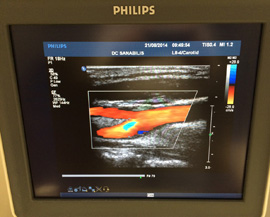

Preiskave z ultrazvokom opravljamo v okviru koncesije na napotnico ter samoplačniško.

Opravljamo naslednje preglede: